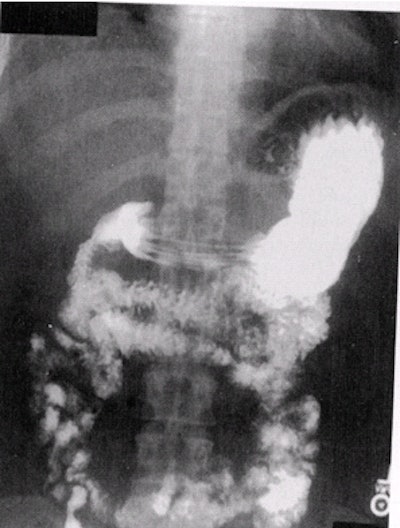

![]() |

| Single-contrast UGI overhead PA film. Note that the stomach is imaged at the superior aspect of the film so as to visualize as much of the small bowel as possible. Image courtesy of Dr. Naveed Ahmad. |